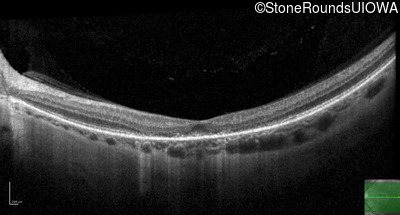

Optical Coherence Tomography - Right - 20/300

Exemplar / OCT Stack